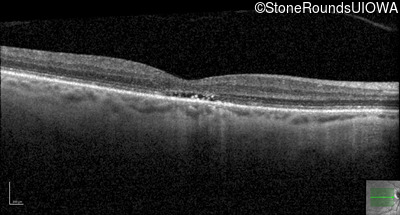

OD OS

This 30 year old man has had reduced acuity and abnormal color vision OU since early childhood.

The clinical features supporting the diagnosis of blue cone monochromacy in this patient include: stable reduced acuity, photophobia and very poor color vision since early childhood, a normal fundus appearance, normally sighted parents and three similarly affected male relatives on the maternal side of his family.

Age at visit: 30 years